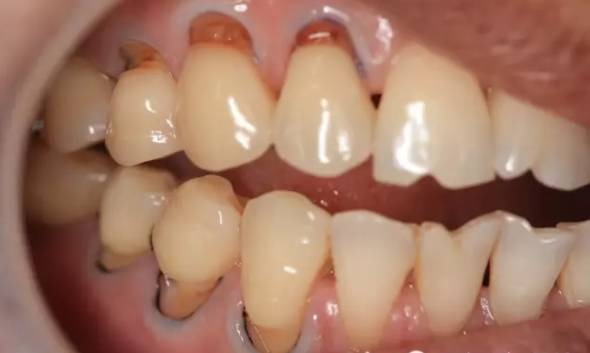

很多人觉得刷牙只不过是一件小事情,其实不然。现在,请你先对照镜子,张开嘴,看看你的牙齿根部,是不是像下图一样,隐隐约约有些凹下去了?如果是,那你就得当心了!

与普通蛀牙不同,出现这种情况,你的牙齿危险了!医学上称之为“楔状缺损”!

这种横槽就是“楔状缺失”!由于它外形酷似木匠用的楔子,因此称为“楔状缺损”。

楔状缺损是发生在牙齿唇、颊面颈部的慢性硬组织缺损,呈“V”状,由于它的外形酷似木匠用的楔子,因而得名楔状缺损。多见于前牙或者双尖牙的唇面,以中老年患者居多。

横向刷牙的习惯,是牙齿一颗颗掉了的“罪魁祸首”。医生表示,横着刷牙特别是横着使劲刷牙,时间长了,易造成牙齿颈部的楔状缺损损害,牙齿表面刷出一道道槽沟,进而形成牙髓炎、牙疼、牙变色、牙变死等。此外,酸、细菌、挤压的作用,也会造成牙齿“楔状缺损”。